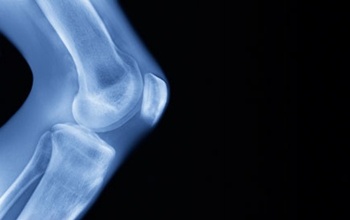

우리나라 60세 인구의 절반이상이 앓고 있다는 퇴행성 관절염. 이러한 퇴행성 관절염은 끊임없는 관절운동으로 연골이 닳아 뼈와 뼈가 맞닿아 발생하게 되는 질환을 말한다. 이렇게 관절 사이에서 완충역할을 해주던 연골이 닳아 없어지면서 발생되는 통증은 상당히 심각하다.

더욱이 연골이 마모된 이후에는 충격흡수가 잘 되지 않는 상태이기 때문에 이러한 상태로 일상생활을 진행 하다 보면 지속적인 뼈의 마찰로 인하여 자연스럽게 뼈와 인대까지 손상을 받게 될 수 있다. 이러한 극심한 통증은 자연스럽게 노년의 삶의 질 또한 현저히 떨어뜨리게 된다.

퇴행성 관절염 초기라면 약물치료와 물리치료 등 보존적인 방법만으로도 통증 조절이 충분히 가능하다. 그럼에도 불구하고 퇴행성 관절염이 진행되어 계속적인 통증으로 인하여 고통스럽다면 마지막 수단으로 수술적인 방법을 생각해야 되는데 그 방법이 인공관절 수술이다. 인공관절 수술은 반복 되는 관절염의 통증을 차단시켜 수술 후에 발생하는 통증을 최소화하여 정상적인 일상생활을 할 수 있게끔 도와준다.

금천구에 위치한 관절전문 희명병원(이사장 최백희) 정형외과 김정민 진료부장은 “무릎통증으로 고생하며 병원을 찾는 분들의 경우 무턱대고 인공관절 수술을 시행하는 것이 아니라 검진결과를 보고 치료방법을 선택하게 됩니다. 대부분 연골의 마모된 부분이 심각하거나 더 이상 관절의 정상적인 활동이 불가능 하다고 판단 되면 인공관절 수술을 권유하게 되죠. 또는 관절 운동 범위가 현저하게 떨어져 제대로 된 보행이 불가능하거나 퇴행으로 인한 관절변형이 매우 심각한 경우에도 시행 됩니다”라며 퇴행성 관절염에 인공관절 수술이 적용되는 경우에 대해 설명했다.

인공관절의 수명은 보통 약 15-20년 정도 되는 것으로 알려져 있지만 환자의 관절 상태와 관리 방법에 따라서 조금씩 차이가 생길 수는 있다. 무엇보다도 인공관절 수술이 굉장히 세말한 수술이기 때문에 수술 받기 전에 반드시 전문성과 임상경험을 갖춘 전문의와 상담을 통해 수술여부와 수술방법을 결정하는 것이 좋다. 인공관절 수술 후에는 꾸준히 정기검진을 받아주는 것이 중요하며 재활 치료 및 적절한 관리를 해주어 오랫동안 인공관절을 사용하도록 하자. /생활경제팀 osenlife@osen.co.kr